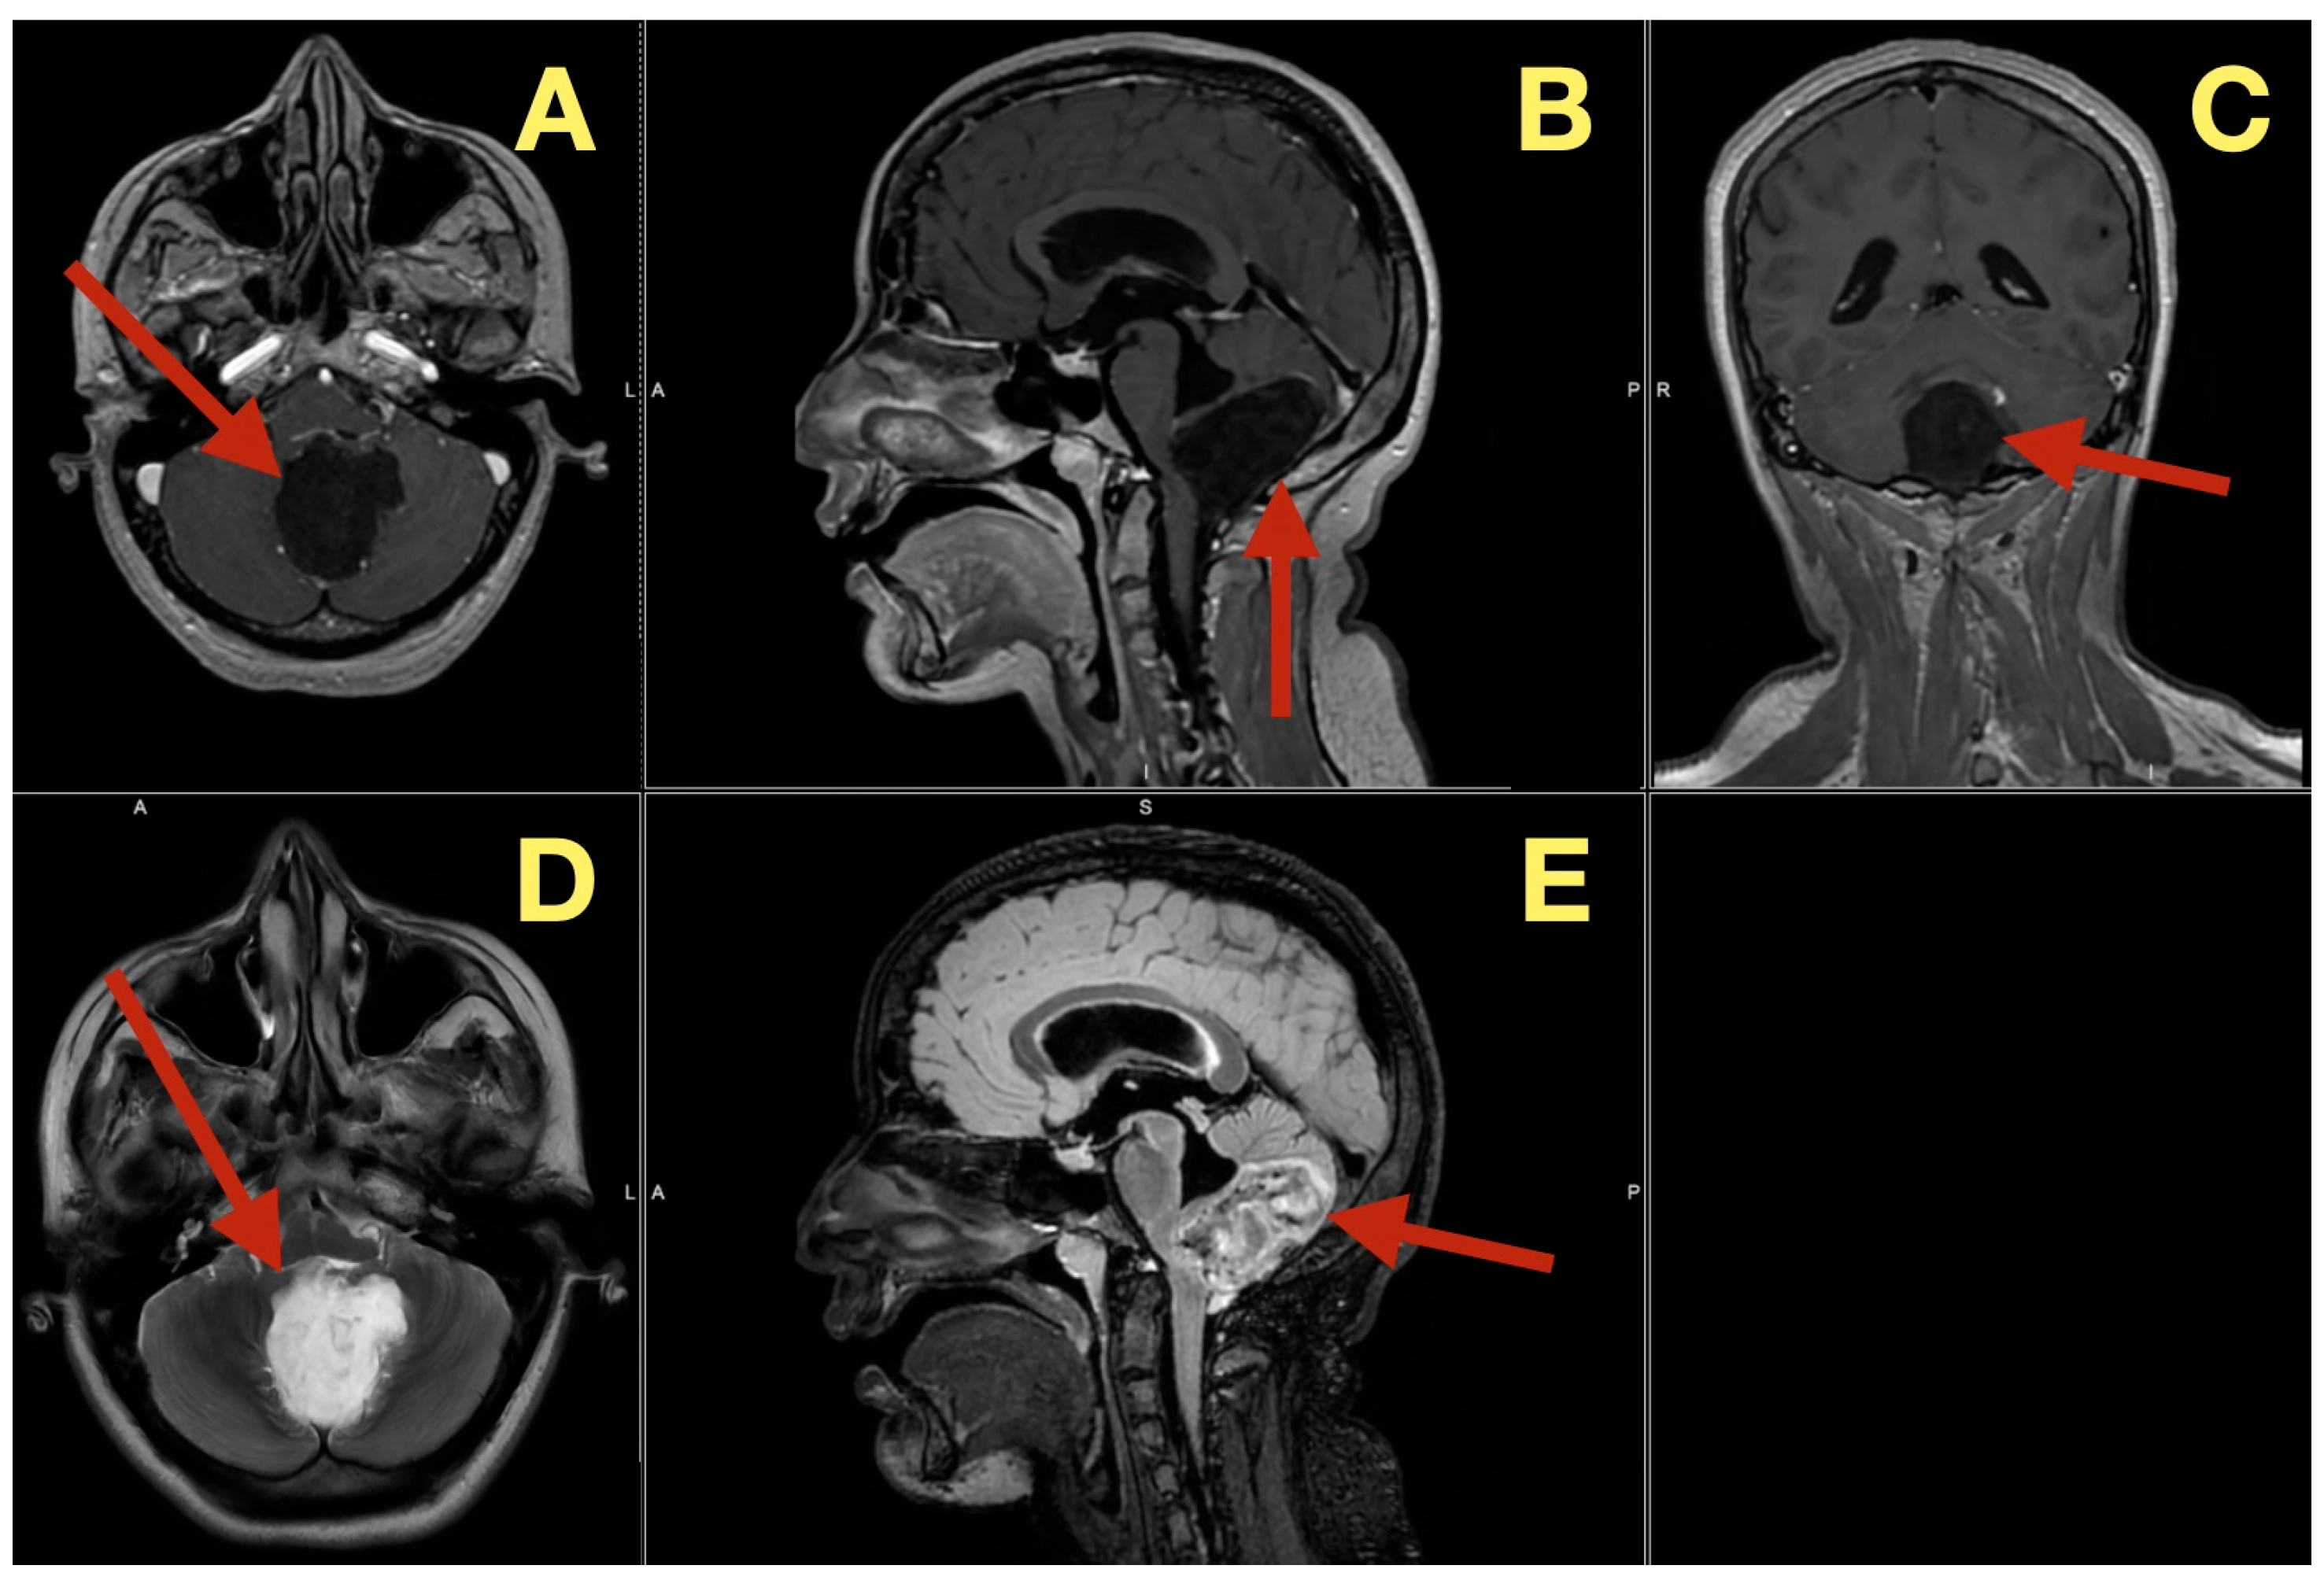

The preoperative MRI demonstrated a multilobulated mass within the fourth ventricle which was molded to the roof and cavity of the fourth ventricle. The mass arose from the inferior portion of the vermis and draped over the superior medullary velum and had smooth interfaces with the surrounding parenchyma which it displaced but did not invade. The mass was uniformly hypointense on T1 images; however, on T2/FLAIR images, the mass had hyperintensity with internal lobulation. The mass marginally compressed the uvula and nodulus and compressed the posterior surface of the pontine-medullary tegmentum. The foramen of Magendie was obliterated and both foramina of Luschka were narrowed resulting in an upstream flow void in the ventricles and a rim of periventricular interstitial edema. This created the hydrodynamic environment responsible for the patient’s symptoms. The worsening headache and vomiting in the morning, the papilledema, and nuchal rigidity resulted from the hydrodynamic environment. The avascular nature of the mass and the CSF conforming surface of the mass, as well as its central location, strongly suggested the possibility of an epidermoid cyst vs. a vascular neoplasm. The image-symptom correlation was excellent: the axial ataxia and titubation were due to compression of the fastigial nucleus and the vermian midline; the gaze-evoked nystagmus was due to disruption of the flocculonodular circuitry along the fourth ventricular roof; and the intracranial hypertension was due to obstruction of the caudal apertures. The morphology and epicenter of the mass were most consistent with a posterior fossa midline epidermoid tumor of Type 2 (fourth-ventricle epicenter) with a dominant relationship to the tela choroidea and cerebellomedullary fissure, anticipating a roof-centered growth pattern and possible focal adherence to the ventricular floor.

On the axial post contrast T1 plane (Figure 1A), the mass occupied the ventricular space like a mold, did not enhance, and was in the midline. The medial surface of the mass was in contact with the cerebellar vermis and the lateral surface of the mass slightly indented the tonsillar surfaces without penetrating into the parenchyma. On the mid sagittal T1 view (Figure 1B), the mass was in contact with the inferior vermis and caused an upward bowing of the superior medullary velum and flattening of the dorsal medulla and this explained the patient’s episodes of pressure-induced vomiting by mechanical stimulation of the area postrema. The coronal T1 reconstruction (Figure 1C) clearly demonstrated that the mass was in the midline and caused an equal compression of the two outlet recesses and was consistent with the absence of laterality in the patient’s deficits. On T2 (Figure 1D) and mid sagittal FLAIR (Figure 1E), the mass’ fluid-like appearance and internal lobulation were prominent; the surface of the mass was molded to the fourth ventricular CSF and not invading the fourth ventricular CSF, and this was a classic finding for this type of mass and accounted for the unusual severity of the fastigial/vermian hub being compressed and not destroyed.

Figure 1.

Preoperative MRI of the posterior fossa. (A): Axial post-contrast T1: non-enhancing, lobulated mass centered in the fourth ventricle (arrow). (B): Mid-sagittal T1: inferior-vermis contact with upward bowing of the superior medullary velum and dorsal brainstem compression (arrow). (C): Coronal T1: strict midline localization with symmetric crowding of the ventricular outlets (arrow). (D): Axial T2: intrinsically high signal with molded margins against cerebellar tonsils (arrow). (E): Mid-sagittal FLAIR: high signal lesion with effacement of Magendie and narrowing of Luschka, concordant with obstructive hydrocephalus (arrow). Radioclinical correlation: vermian compression → truncal ataxia/titubation; flocculonodular disturbance → gaze-evoked nystagmus; outlet occlusion → intracranial hypertension.